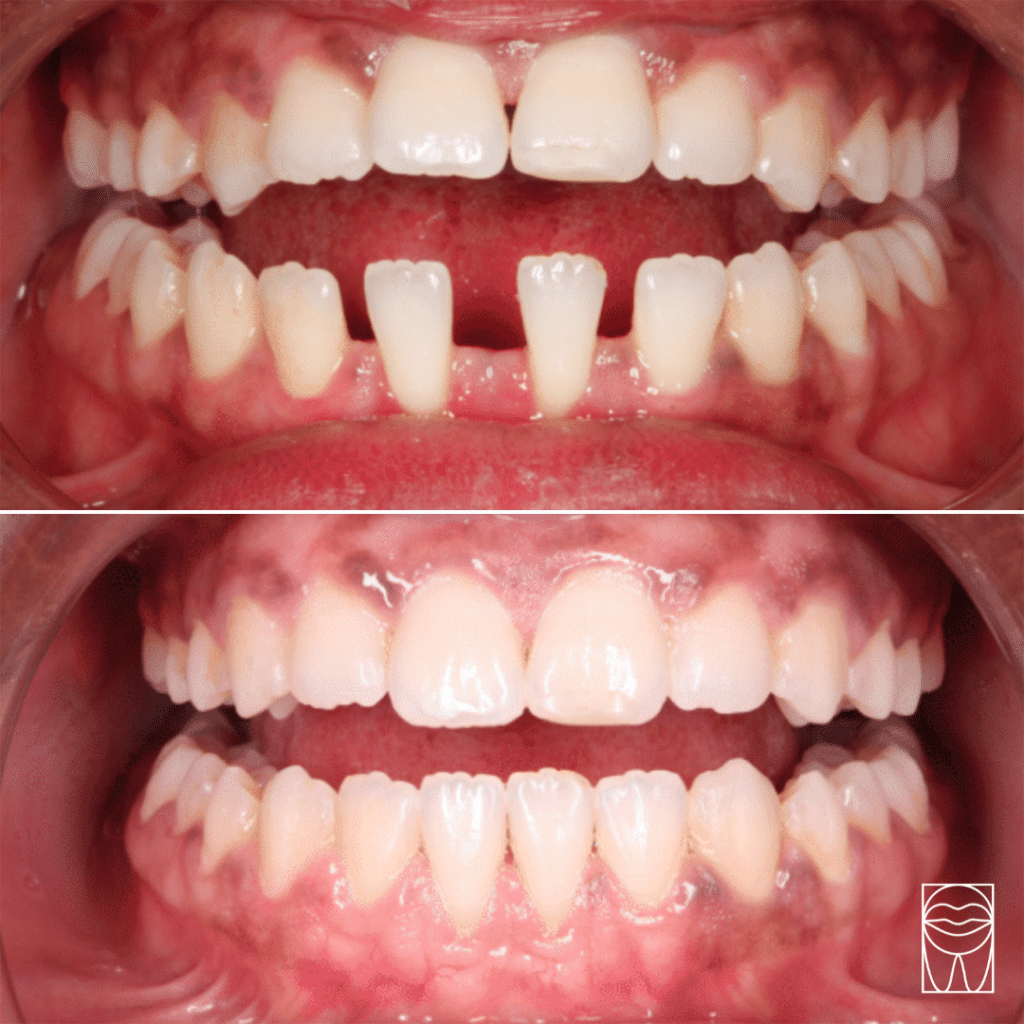

Chevauchement dentaire

Malposition

Le chevauchement dentaire (appelé également encombrement dentaire). S’observe lorsque les dents se superposent en raison d’un manque d’espace, donnant un aspect “tordu” au sourire.

espacement

dentaire

Malposition

L’espacement dentaire (nommé également diastème). Comme son nom l’indique, cette imperfection désigne un ou des écarts entre les dents. Le diastème inter-incisif est le cas le plus fréquemment rencontré, il s’agit des fameuses “dents du bonheur”.

Nos résultats